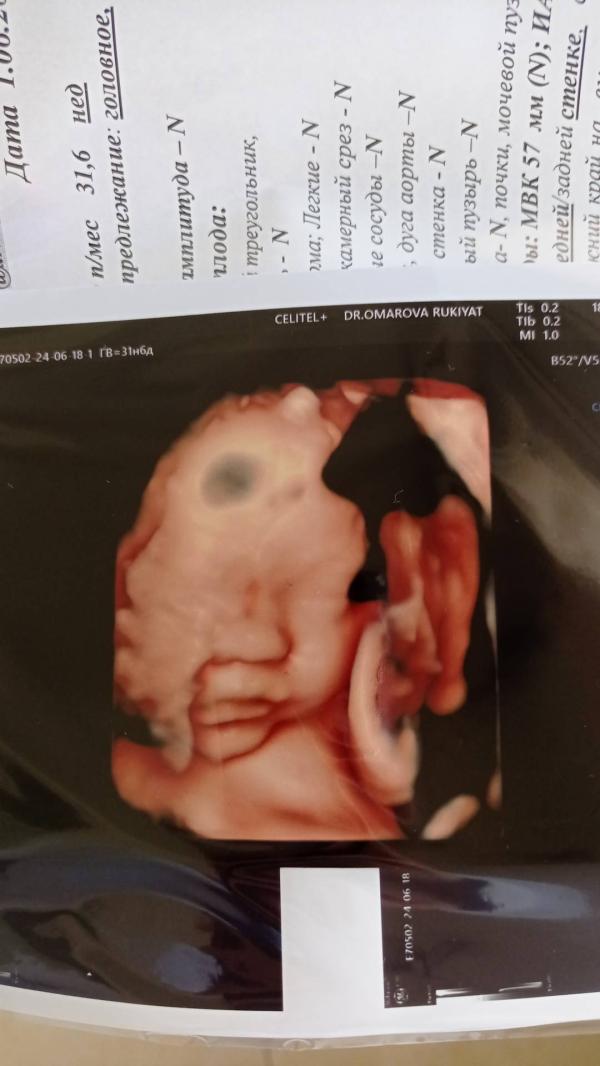

Так быстро время летит. Ещё недавно я бегала с пузой. Ждала встречи с тобой.🥰 Радовадась каждому твоему пиночку. Чувствовала твое икание🥲. Скоро будет 4м إن شاء الله 🥰 Алх1ямдуЛиллагь за то что ты есть у меня